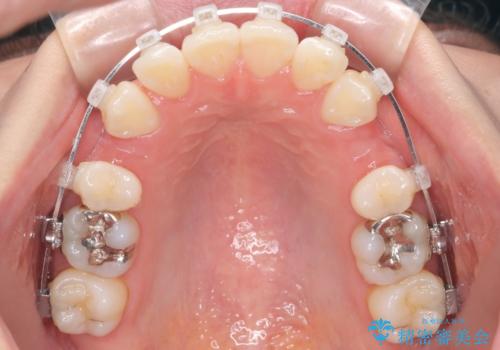

- 出っぱによる口元の閉じにくさを主訴に来院されました。上顎の出っ歯と上下顎叢生も認められたため、上下顎両側4番抜歯を行い、ワイヤー矯正で治療する治療計画を立てました。

上顎にはMI(マイクロインプラント)を埋入して固定源とすることで出っ歯の改善を図りました。

少しスペースクローズに時間がかかりましたが、MIを用いたワイヤー矯正で

主訴である出っ歯と叢生が改善されました。口も閉じやすくなり、スッキリとした口元になりました。